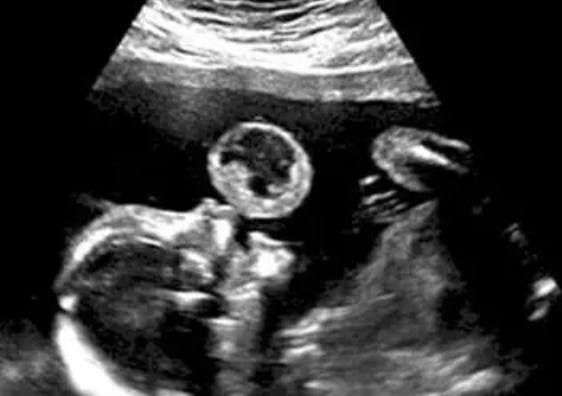

A Facebook post recently went viral, claiming that a young boy, approximately two years old, was found wandering alone at night in either Hereford or King’s Lynn by a police officer named “Deputy Tyler Cooper.” The post included an image…